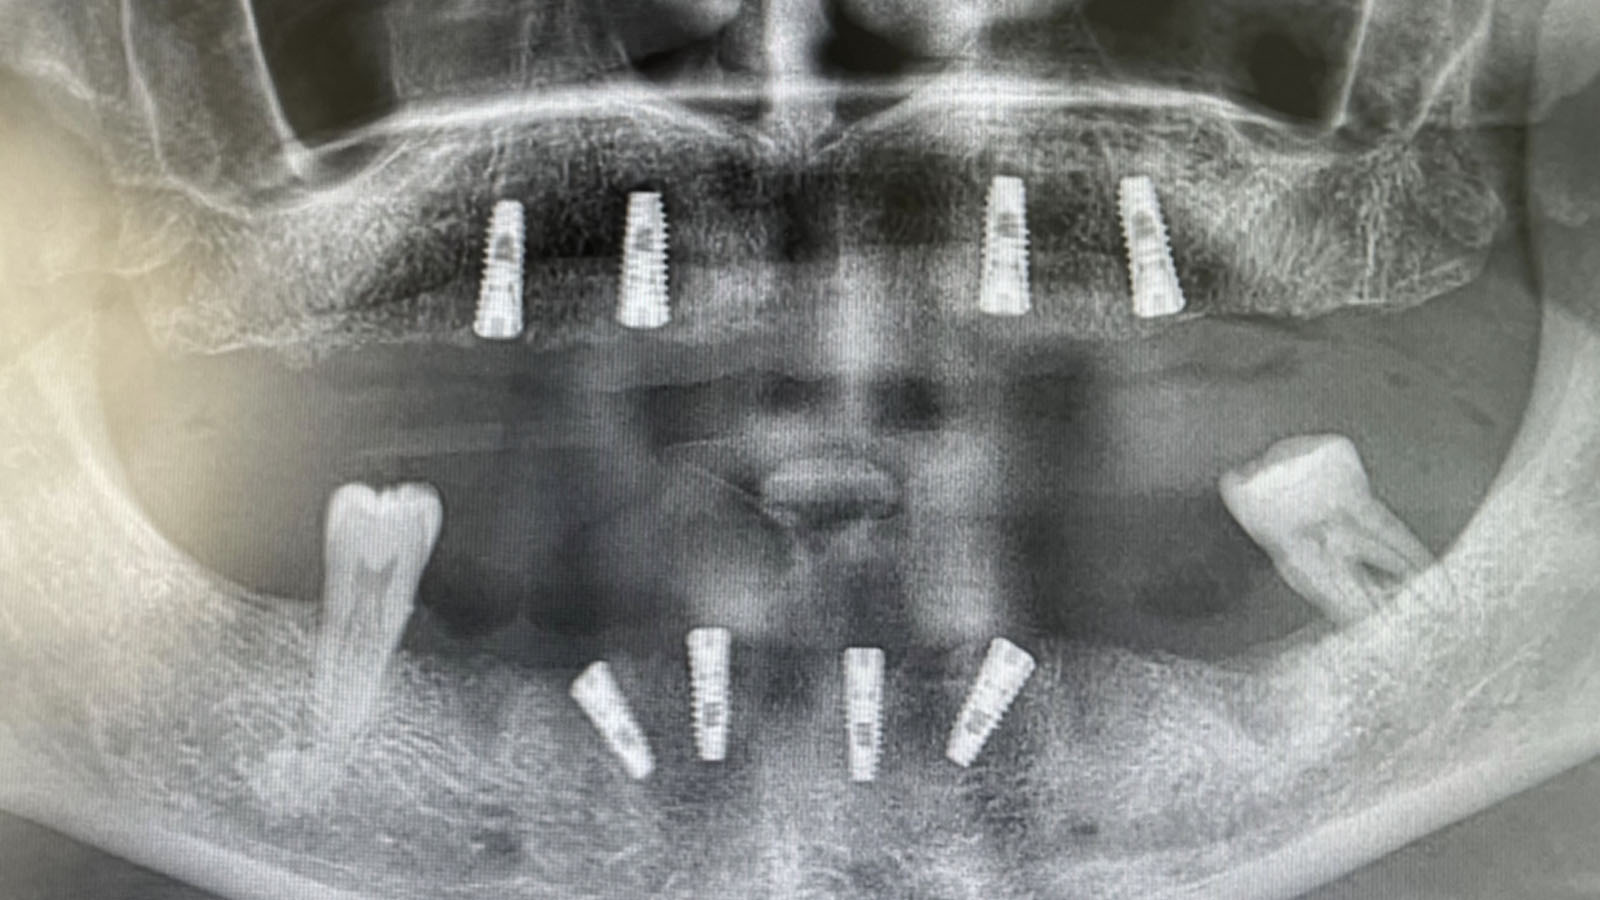

First of all a detailed clinic and radiological examination should be done to patients for who All On Four treatment is planned. By making meausrements through computerized tomography (BT) a suitable plan is made for the patient.

All On Four procedure is composed of two parts as surgery and dental prothesis process. After 4 pieces of dental implants are applied to the patient on the first day of treatment, temporary dental prothesis is fixed on dental implants on the same day. 3 months later permanent teeth prothesis is applied to patient